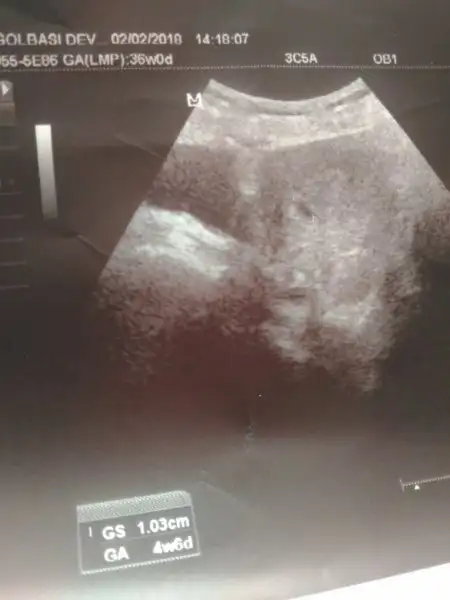

Aramızda 3 hafta var canım ama çok çabuk büyüyorlar diğer kontrolde benim de öyleydi:) Alkah sağlık versin çok çok hızlı büyüyorlar karnımızda:)ay maşallah amin canım,benm bebiş dha nokta gibi pek bişeye benzemiyo :)

Yok canım şu kese konumu efsanesi var ya ilk görüntü sola yakınsa erkek sağa yakınsa kız derler ona bakarak dedim allah gönlüne göre versin